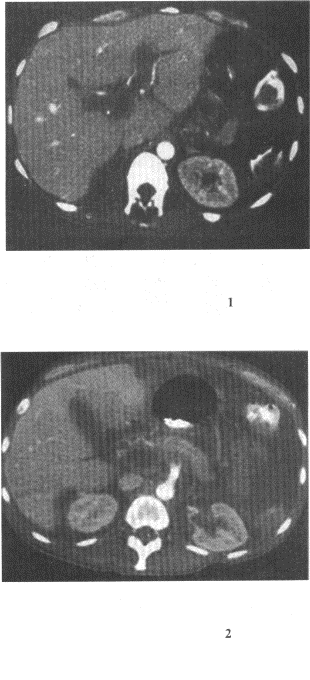

患者,男,54歲,左側腰痛,伴間歇性血尿2個月余,體格檢查左腎區叩擊痛,CT增強掃描如圖所示。

12.結合圖像所示,下列哪項描述正確

患者30歲,女性,右上腹持續性痛,腹脹,胸悶,食欲減退,消瘦。實驗室檢查,甲胎蛋白血清AFP試驗陽性血清堿性磷酸酶(ALP)增高,CT示肝右前葉病灶。

17.分析圖像,結合病史,最可能的診斷是